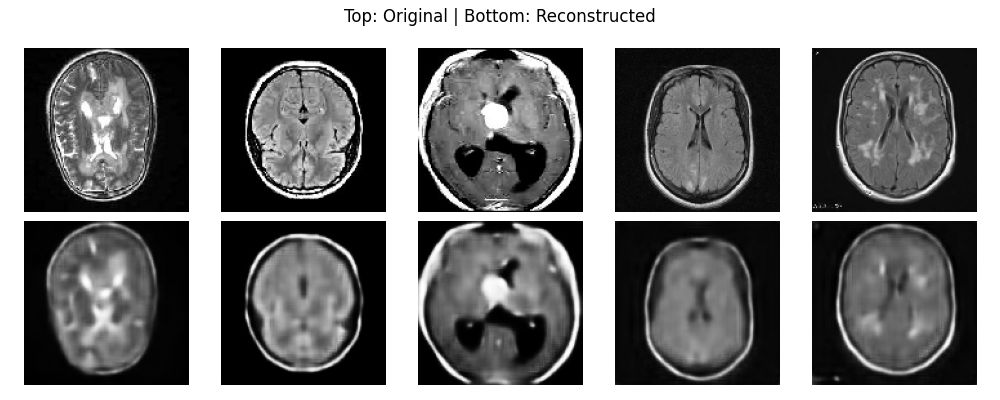

Antes de construir el clasificador, debemos verificar que nuestro autoencoder esté aprendiendo características significativas y no simplemente memorizando ruido. Para hacer esto, observamos la pérdida de reconstrucción y comparamos las imágenes de entrada con las salidas generadas.

La inspección visual confirma que el «Espacio Latente» contiene suficiente información para reconstruir la anatomía mientras filtra algo de ruido de alta frecuencia.

[Insert Brain reconstruction.jpg here]

Pie de foto: Arriba: MRI original | Abajo: Imagen reconstruida. Observa cómo se preservan la estructura general y el área del tumor.